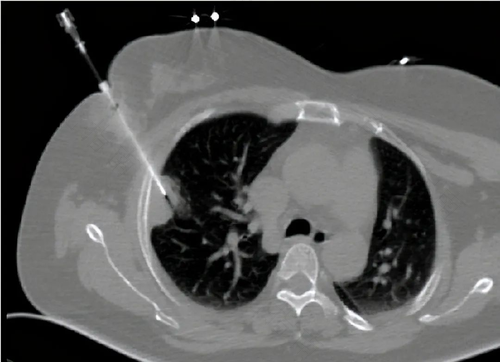

肺穿刺是一种针对肺部问题进行检查的临床检查方式。如果患者肺部有问题,一般徐要听从医生安排进行肺穿刺检查。但是很多患者担心进行肺穿刺检查会有生命危险。那么,进行肺穿刺检查危险吗?

肺穿刺检查由于涉及肺部,所以是存在一定的危险性。面对这种情况,需要医生细心,患者密切配合,才能降低检查风险,提高检查成功率。因此肺穿刺检查时,患者呼吸应该平稳,不要咳嗽。而且在检查前要进行一些列身体检查,一边医生能够正确定位,提高穿刺成功率。

其实,医生进行肺穿刺时,需要吸空支气管内液体进一步检查,确定肺部情况,然后对某些疾病进行治疗,必要时需要注入药物达到治疗目的。虽然患者能够成功做完非穿刺检查,但是肺穿刺检查是有并发症存在的。如果患者一时不注意,容易影响身体恢复。

而肺穿刺检查的并发症有气胸、胸膜腔出血以及其他器官气体栓塞等,其中气胸、肺内出血是最常见的并发症。若是气胸问题,这种情况可自行恢复,患者不用担心。但是如果是肺内出血情况,则需要及时通知医生,及时进行治疗。